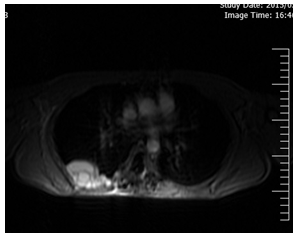

Figure 2: MRI showing extradural cystic lesions at T7-T8 level. There was cerebrospinal fluid (CSF) like signal intensities on T1- and T2- weighted images.

The magnetic resonance imaging (MRI) of thoracic spine revealed multiple well-defined extradural cystic lesions at T6-T8 level. There was cerebrospinal fluid (CSF) like signal intensities on T1- and T2- weighted images (Figures 3-5).